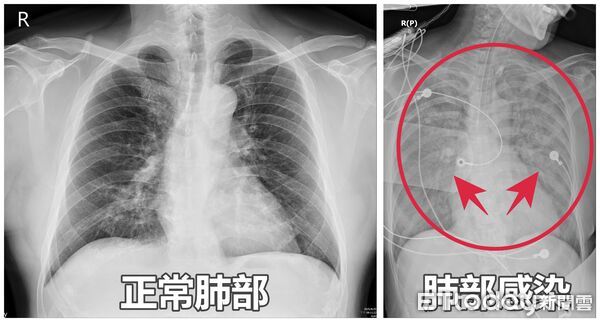

正值農曆七月,任何風吹草動都可能讓人心頭一緊。一名65歲李姓闆娘日前因嗜睡、咳嗽、全身無力及胃口不佳掛急診,家人反映患者猶如「靈魂出竅」,檢查後才發現闆娘血氧僅剩90%, X光更發現「雙肺白掉一大片」,研判是肺炎惹禍,緊急送至加護病房觀察照顧,所幸經用藥治療後,一週後順利出院,不是鬼月撞邪才精神散渙。

謝逸安指出,包括流感、呼吸道融合病毒(RSV)以及肺炎鏈球菌等,都是常見社區型肺炎的呼吸道病原,尤其60歲以上長者、孕婦、兒童以及免疫力較弱的慢性病患,更是感染高風險族群,往往一感冒就造成「大白肺」,甚至不少民眾病發前身體並無明顯徵兆,直至入院後才知道已經敗血症,此時已影響多個器官。

謝逸安提醒,民眾若染上肺炎,肺部所產生的痰液,會先造成支氣管及肺泡堵塞、影響呼吸,嚴重者會危及生命,雖然多數病人只要盡早診斷治療,多半能順利康復,但仍有不少民眾常會自行購買成藥服用,以為「可以止咳就好」,導致病情越來越嚴重,甚至得長期住在加護病房難以脫身。